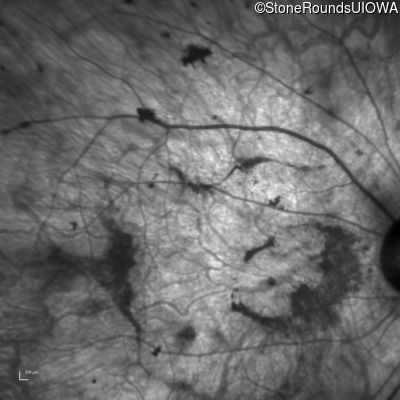

Age at visit: 38 years

OD OS

This 38 year old woman had normal vision until age 22 when she noticed poor night vision when working as a camp counselor after college. Her hearing loss was first noticed at age 3 and was correctable with hearing aids.